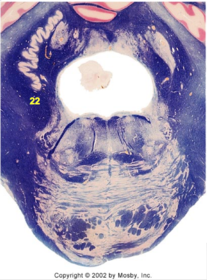

| CN IX | |

| Inferior cerebellar peduncle | |

| Inferior olivary complex | |

| Dorsal cochlear nucleus | |

| Inferior vestibular nucleus | |

| Medial vestibular nucleus | |

| Spinal nucleus of V | |

| Spinal tract of V | |

| Medullary pyramids | |

| Solitary nucleus | |

| ALS | |

| Medial lemniscus | |

| Medial longitudinal fasciculus | |

| Ventral cochlear nucleus | |

| Anterior spinocerebellar tract | |

| Central tegmental tract | |

| Olivary internal arcuate fibers | |

| Solitary tract | |